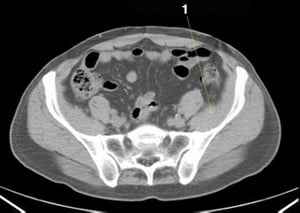

CT-Scan von Abdomen und Becken mit normaler Anatomie ohne Kontrastmittel (Folie 25)

1 = Colon sigmoideum.

© Springer Science+Business Media